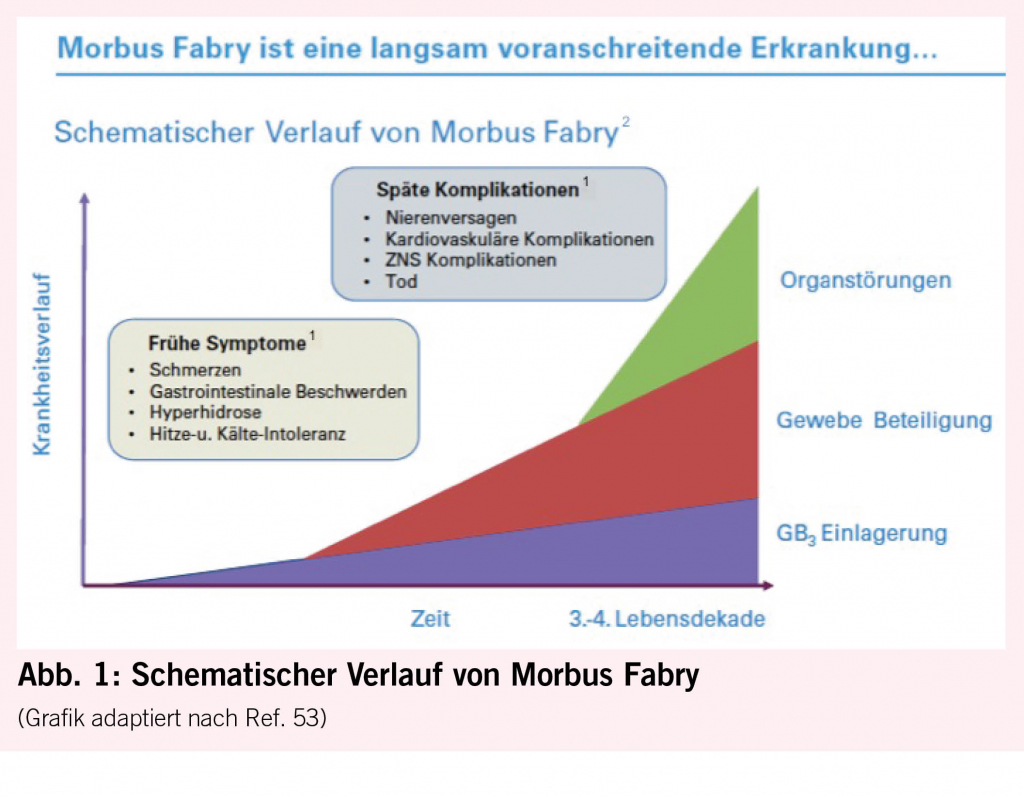

Bei Morbus Fabry unterscheidet man klassische von atypischen Krankheitsmanifestationen. Der klassische Phänotyp tritt bei homozygoten Männern auf, die keine Enzymaktivität aufweisen und daher oft schon früh in der Kindheit oder Jugend unter febrilen Schmerzkrisen, Akroparästhesien, Hypohidrose, Angiokeratomen und gastrointestinalen Beschwerden, vor allem Durchfall, leiden. Durch progrediente GB3-Ablagerungen kann es dann im Erwachsenenalter zu schweren Schädigungen des Herzens (Herzrhythmusstörungen und Herzinsuffizienz), der Nieren (bis hin zur Dialyse oder Nierentransplantation) und des Gehirns (zerebrovaskuläre Ereignisse) kommen (Abb. 1). Während heterozygote Frauen früher oft nur als asymptomatische Konduktorinnen galten, ist heute bekannt, dass sie genauso auch einen Vollphänotyp entwickeln können, der eher später im Leben auftritt als bei Männern. Die atypische Form ist durch eine reduzierte, aber noch nachweisbare Enzymaktivität gekennzeichnet, die mit einem späteren Symptombeginn mit Oligosymptomatik und isolierter Herz- oder Nierenbeteiligung einhergeht. Die letztere Form wird oft bei der Abklärung einer idiopathischen LVH (6, 9) oder Niereninsuffizienz entdeckt.

Das Herz ist mit 68% das Organ mit der häufigsten intrazellulären GB3-Akkumulation (10,11), die in den Myozyten, Herzklappen und Gefässendothelien stattfindet und neben der Infiltration auch einen inflammatorischen und oxidativen Stress verursacht (12). Als Folge leiden über die Hälfte der männlichen Fabry-Patienten und 18- 28% der Frauen mit Morbus Fabry (13, 14) unter einer konzentrischen LVH (siehe Abb. 2) mit einer typischerweise früh einsetzenden diastolischen Dysfunktion (15,16) und im Verlauf restriktivem Füllungsmuster (17, 18). Die LVH bei Fabry unterscheidet sich in der Regel durch das Fehlen einer Ausflussobstruktion von einer idiopathischen hypertrophischen Kardiomyopathie (4) und kann auch mit einer rechtsventrikulären Hypertrophie und Dysfunktion einhergehen (19). Während bei Männern erste kardiale Beschwerden mit durchschnittlich 33 Jahren einsetzen, wurde bei Frauen ein späterer Beginn um das 40. Lebensjahr beobachtet (7). Typischerweise kommt es im Verlauf zu einer Herzinsuffizienz mit erhaltener Ejektionsfraktion (7). Aufgrund der Endothelablagerungen kann es zudem oft auch zu einer endothelialen Dysfunktion (20, 21) kommen. Möglich ist auch eine mikrovaskuläre Dysfunktion, die Angina pectoris verursacht (22). Die fortgeschrittene Fabry-Kardiomyopathie (FK) ist durch eine fibrotische Umwandlung des linken Ventrikels, die typischerweise infero-baso-lateral beginnt und nach transmural fortschreitet, gekennzeichnet (23). Diese Fi-broseareale können Rhythmusstörungen (siehe Abb. 3), darunter Sinusbradykardien, höhergradige AV-Blockierungen, und Kammertachykardien hervorrufen und infolge zum plötzlichen Herztod führen (24-26). Auch Vorhofflimmern ist bei Fabry-Patienten häufig zu finden, wobei die Inzidenz vier Mal so hoch ist wie in der Normalbevölkerung, bei über 50-jährigen Patienten sogar zwölffach erhöht (25). Bei der fortgeschrittenen FK kommt es gelegentlich auch zur Herzklappenschädigung, insbesondere zur Insuffizienz der Aorten-, Mitral- oder Trikuspidalklappe (24) sowie Erweiterung der Aortenwurzel (27). Eine weitere typische Veränderung ist ein prominenter Papillarmuskel (28) (Abb. 2).